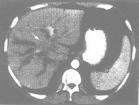

CT或螺鏇CT:原發性腫瘤和中央型病變範圍的最佳檢測方法是CT掃描。螺鏇CT可更好地評估胸廓病變的範圍,顯示在胸部平片上無法顯示的小的原發性或繼發性結節以及淋巴結擴散。